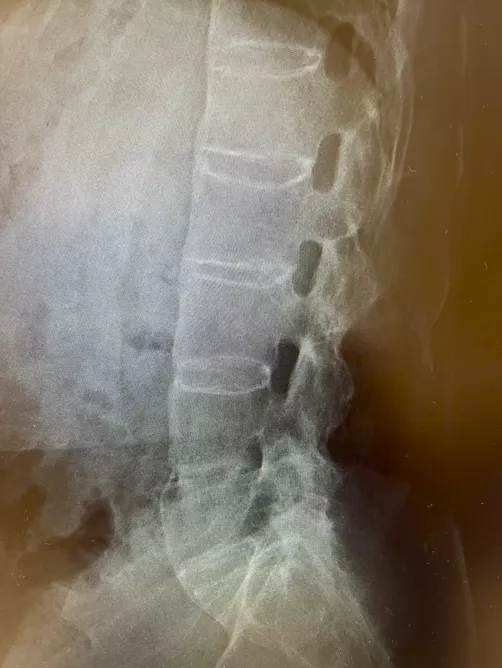

若年男性に発症した、運動により改善して安静により改善しない3か月以上持続する炎症性腰背部痛の所見と血清反応陰性、CRPの上昇より脊椎関節炎を疑った。単純X線では両側仙腸関節に関節裂隙全体の強直を認めgrade4の仙腸関節炎の所見であった(写真1)。また、同写真で腰椎の椎体辺縁に沿った硬化像も認めた(写真1)。追加で行った頸椎(写真2)、胸椎(写真3)、腰椎(写真4)単純X線の側面像では全脊椎の強直(竹様脊椎、bamboo spine)を認めた。以上より強直性脊椎炎と診断した。

写真3 単純X線 胸椎側面像

椎体辺縁に沿った硬化像を認める